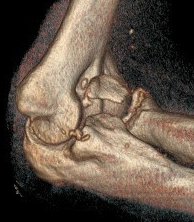

Terrible Triad

Definition

Elbow dislocation with radial head fracture + coronoid fracture + MCL tear

Technique